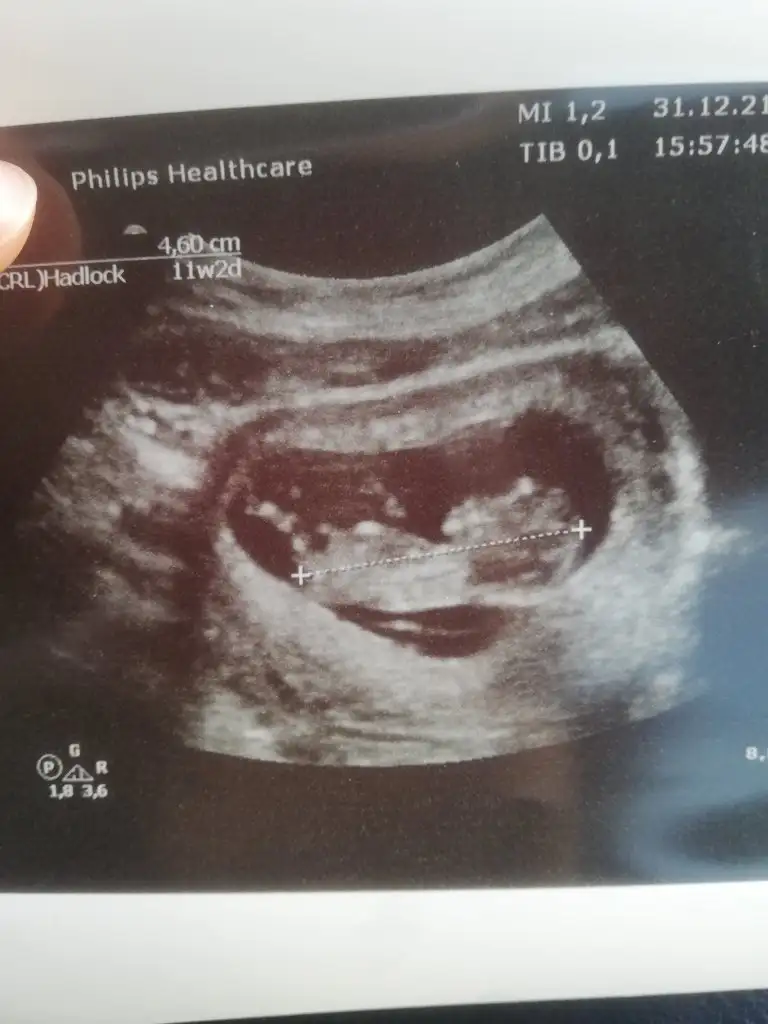

Şimdilik kız yönünde ama en iyi 11 12 13 haftalar olmalı